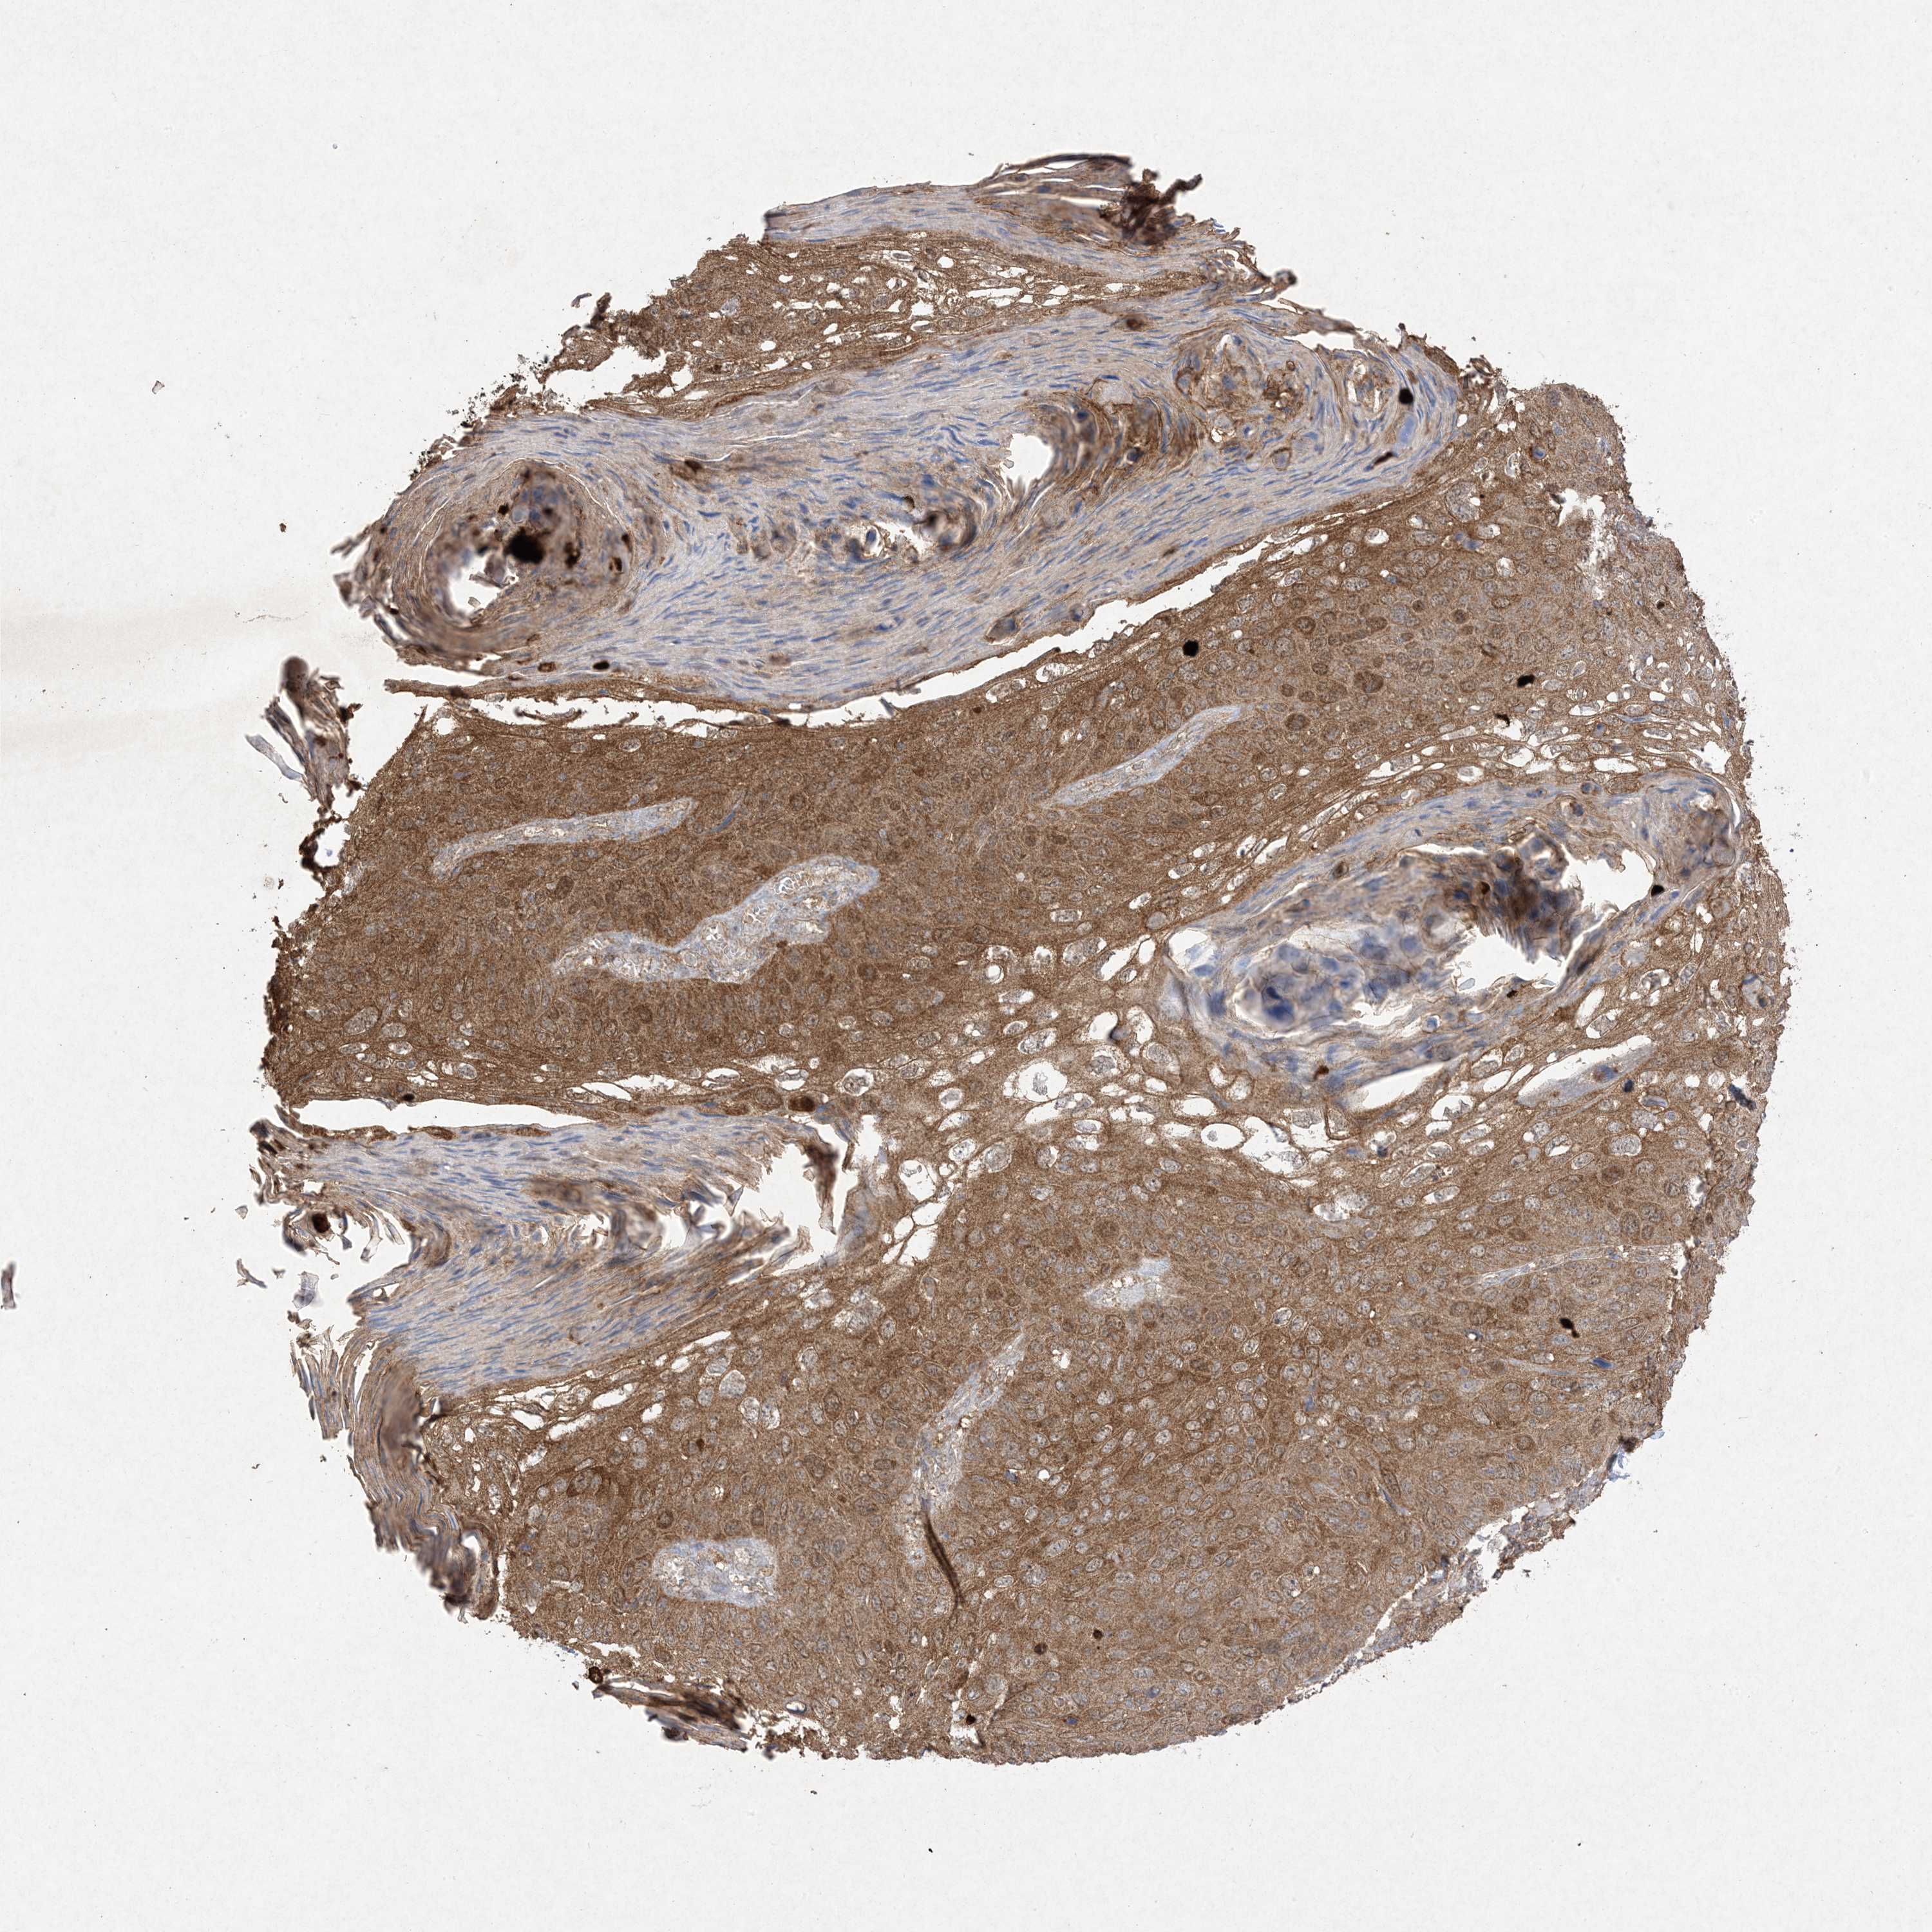

SKIN CANCER - Protein expressioni

A mouse-over function shows sample information and annotation data. Click on an image to view it in a full screen mode. Samples can be filtered based on level of antibody staining by selecting one or several of the following categories: high, medium, low and not detected. The assay and annotation is described here.

Each image is clickable and will lead to virtual microscopy that enables deeper exploration of all samples and also displays staining intensity scores, fraction scores and subcellular localization as well as patient and tissue information for each sample.

Antibody HPA054975

Antibody CAB011464

Antibody CAB035990

Antibody CAB080407

Staining

High

Medium

Low

Not detected

Intensity

Strong

Moderate

Weak

Negative

Quantity

>75%

75%-25%

<25%

None

Location

Nuclear

Cytoplasmic/membranous

Cytoplasmic/membranous,nuclear

Basal cell carcinoma